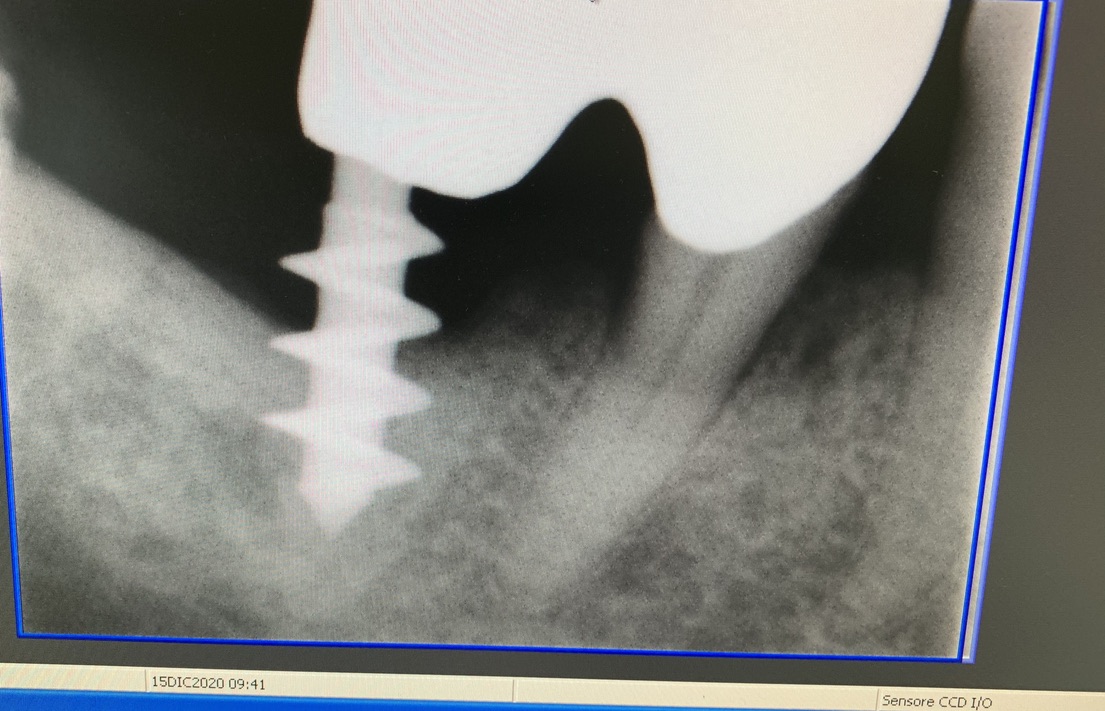

Forma originale dell’impianto di Tramonte. Diametro 5 mm a 3 spire. Gambo diam. 2,1 mm. Collo diam.2 mm x 5 mm di lunghezza. Titanio di grado 2. Il grado 2 consentiva al bisogno di piegare il collo dell’impianto per migliorare il parallelismo. Si tratta di un impianto postestrattivo immediato. Perciò nella stessa seduta estrazione, alesatura maschiatura ed inserimento dell’impianto. Subito seguiti da monconizzazione e da confezione di corone provvisorie in occlusione leggera. Le radiografie fornite evidenziano la situazione a partire dal 2010. La emergenza del collo sottile favorisce la formazione di un manicotto di gengiva densa che protegge dalle periimplantiti. Le spire larghe irradiano lontano dal corpo impianto il carico occlusale favorendo la formazione di un osso più omogeneo.